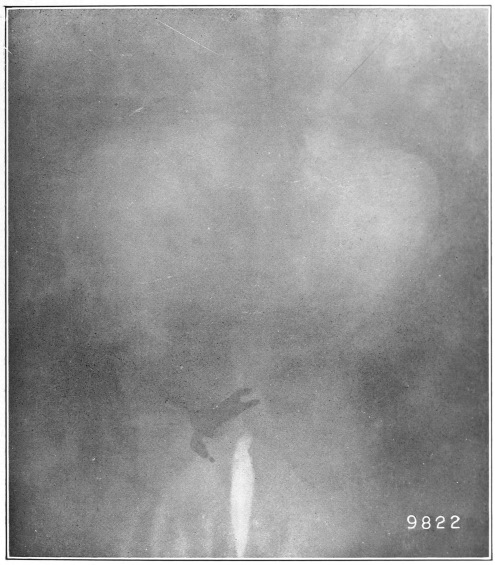

Nine Radiograph Illustrations Showing Mucus Channels and Cavities200

Rebellion of our outraged Internal Economy.